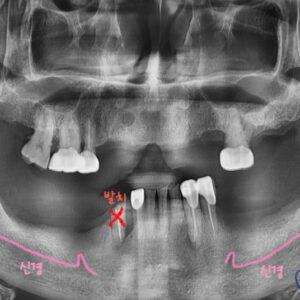

기다린 후

아래 임플란트도 식립을 했고 나머지 치아들도 크라운이 다 올라간 사진입니다.

치료가 마무리 되었습니다.

뼈이식 한 부분도 튼튼하게 잘 고정되어있네요ㅎㅎ